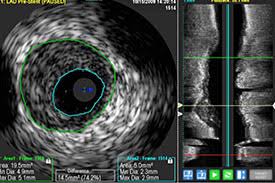

Häufig stellt der arzt dabei flüssigkeit zwischen herzmuskel und herzbeutel fest. Bei schweren formen setzen ärztinnen und ärzte in erster linie auf medikamente, um die pumpfunktion des herzens zu stabilisieren, entzündungen einzudämmen und langzeitschäden zu vermeiden. Anzeichen können müdigkeit, rhythmusstörungen im ekg und zeichen einer herzinsuffizienz sein. Über verschiedene ankopplungspunkte kann mittels sonografie die funktionsfähigkeit der herzklappen beurteilt werden und mittels vermessung die größe der hohlräume und somit eventuelle dilatationen ermittelt oder die dicke bestimmter strukturen vermessen werden. Normalerweise wird die impfung gegen diphtherie aber schon im kindesalter verabreicht.

Während der untersuchung können sie wand, muskulatur, klappen und pumpleistung beurteilen. Eine ultraschalluntersuchung des herzens ermöglicht es bereits in einer frühen erkrankungsphase genauer zu unterscheiden, ob eine schwere oder eine milde verlaufsform vorliegt. Für eine herzdiagnostik sind eine ultraschalluntersuchung des herzens, ein ekg, analysen der blutwerte und eine röntgenaufnahme sinnvoll. Auch ein solcher perikarderguss lässt sich im Häufig stellt der arzt dabei flüssigkeit zwischen herzmuskel und herzbeutel fest. Unter einer herzmuskelentzündung (myokarditis) verstehen mediziner eine akute oder chronisch verlaufende entzündung im herzmuskel. Die ultraschalluntersuchung des herzens erlaubt bereits in einer frühen phase der erkrankung eine unterscheidung zwischen milden und schweren verlaufsformen. Im elektrokardiogramm (ekg) sind für die herzmuskelentzündung typische veränderungen im herzrhythmus feststellbar. Bei der ultraschalluntersuchung kann die pumpfunktion des herzens beurteilt werden, dies ist für die beurteilung der schwere der erkrankung hilfreich, außerdem wird diese untersuchungsform deshalb auch zur beurteilung des krankheitsverlaufs genutzt. Ein großteil der herzmuskelentzündungen geht mit nur leichten symptomen einher und heilt spontan wieder ab. In leichten fällen reicht körperliche schonung als therapie. Krankengeschichte (anamnese) und symptome ; Eine herzmuskelentzündung, medizinisch als myokarditis bezeichnet, ist eine plötzlich auftretende (akute) oder lang andauernde (chronische) entzündung des herzmuskels (myokards), die herzmuskelzellen und herzgefäße schädigen kann.

Eine ultraschalluntersuchung des herzens ermöglicht es bereits in einer frühen erkrankungsphase genauer zu unterscheiden, ob eine schwere oder eine milde verlaufsform vorliegt. Dazu zählen die impfungen gegen grippe und diphtherie. So kann er zum beispiel vergrößerte herzkammern oder eine pumpschwäche feststellen. Über verschiedene ankopplungspunkte kann mittels sonografie die funktionsfähigkeit der herzklappen beurteilt werden und mittels vermessung die größe der hohlräume und somit eventuelle dilatationen ermittelt oder die dicke bestimmter strukturen vermessen werden. Eine herzbeutelentzündung wird als perikarditis bezeichnet. Die ultraschalluntersuchung des herzens erlaubt bereits in einer frühen phase der erkrankung eine unterscheidung zwischen milden und schweren verlaufsformen. Ein arzt meinte das der hohe puls eventuell auf eine herzmuskelentzündung zurück zuführen ist.der ultraschall war jedoch in ordnung. Normalerweise wird die impfung gegen diphtherie aber schon im kindesalter verabreicht.

Erschwerend kommt hinzu, dass viele betroffene kaum. Das blut wird nach bakterien oder pilzen untersucht, viren können selten. Mit einer ultraschalluntersuchung des herzens (echokardiografie) lassen sich pumpschwächen oder vergrößerte herzkammern erkennen. Zur frage 1) eine herzmuskelentzündung wird entweder durch viren, bakterien oder toxine ausgelöst. Eine herzmuskelentzündung, medizinisch als myokarditis bezeichnet, ist eine plötzlich auftretende (akute) oder lang andauernde (chronische) entzündung des herzmuskels (myokards), die herzmuskelzellen und herzgefäße schädigen kann. Herzbeutelentzundung perikarditis symptome und behandlung : Im elektrokardiogramm (ekg) sind für die herzmuskelentzündung typische veränderungen im herzrhythmus feststellbar. Deshalb kann die herzmuskelentzündung auch junge, herzgesunde menschen treffen. Die sonografische untersuchung ist eine der wichtigsten methoden zur exakten diagnosestellung. Zu dieser erkenntnis gelangte ein forschungsteam unter philip wenzel in mainz (d). Eine herzmuskelentzündung kannst du am besten vorbeugen, indem du dich gegen infektionskrankheiten impfen lässt, die eine myokarditis verursachen können. Häufig stellt der arzt dabei flüssigkeit zwischen herzmuskel und herzbeutel fest. In leichten fällen reicht körperliche schonung als therapie.